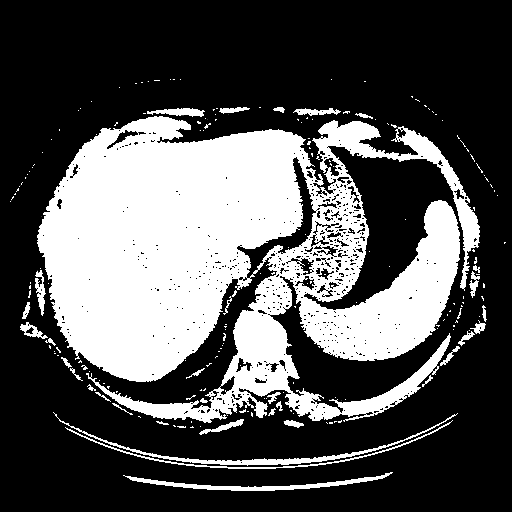

Original VENOUS CT scan

Full window (WL 1023.5, WW 4095 β†’ Low βˆ’1024, High +3071)

Actual HU range: [-1024.0, 3071.0]